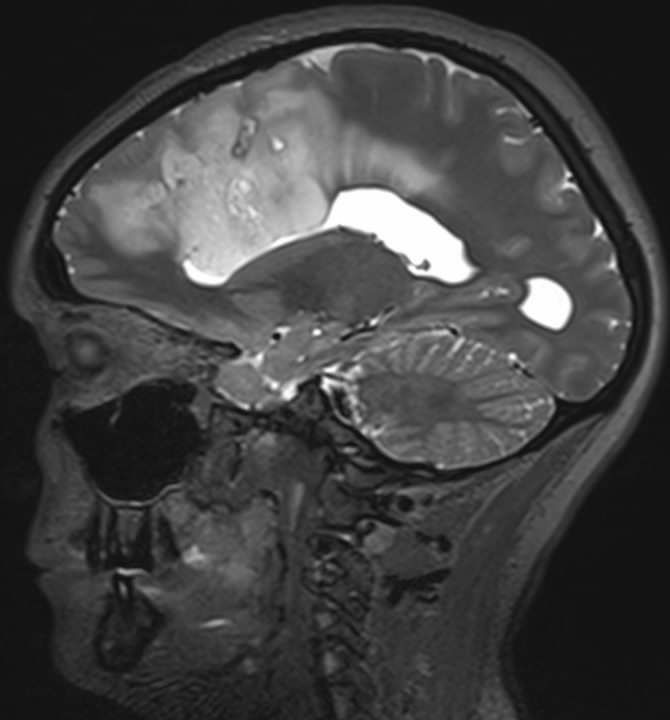

Чуть больше месяца назад в отделение поступила девушка 33 лет с жалобами на периодическую головную боль и однократный эпизод утраты сознания. При МРТ головного мозга выявлена большая опухоль обеих лобных долей с поражением мозолистого тела, размером 11,1х6,5х7,5см. (объем 283,3см3). Основной массив опухоли локализовался в левой лобной доле, подходя вплотную к зонам на коре, отвечающим за движения в правых конечностях и за произношение слов. В глубине опухоль находилась в непосредственной близости от речевых трактов и пирамидных трактов с двух сторон. Повреждение их могло привести к нарушениям речи или парализации пациентки. Мозолистое тело (структура, которая соединяет два полушария мозга между собой) было поражено опухолью на 75%. Разобщение полушарий (пересечение мозолистого тела) может привести к выраженным психическим нарушениям. В структуре опухоли проходили крупные сосуды, питающие до 30% полушарий. Все это делало предстоящую операцию действительно сложной. Так же напрягало еще то, что больную кроме умеренной головной боли ничего больше не беспокоило.

Обсудив все риски с пациенткой и ее родственниками мы выполнили операцию. Т.к. опухоль локализовалась вблизи речевых зон и трактов, операцию выполняли с пробуждением и общением с пациенткой во время удаления опухоли. Стимулируя каждый миллиметр коры и белого вещества головного мозга, мы выявили все функциональные (речевые и двигательные зоны и тракты, их соединяющие) зоны. Во время операции больная активно общалась с нашими помощниками нейролингвистами - Andrey Zyryanov и Гордеевой Елизаветой из команды Olga Dragoy. Сохранность важных мозговых структур отслеживала наш нейрофизиолог Мария Подгурская. Благодаря их помощи нам удалось удалить почти всю опухоль из обоих полушарий и мозолистого тела. Это заняло у нас 7 часов. Операционная бригада, помимо указанных специалистов, состояла из Ольга Вобликова, Алексей Димерцев, Кристина Ключникова, Алексей Корябочкин.

На послеоперационных МРТ видно, что опухоль удалена на 98,3%. Небольшой ее фрагмент в задних отделах пришлось оставить из-за прорастания ей двигательных зон.

Сразу после операции больная меня напугала - она не могла говорить и у нее развилась выраженная слабость в правых конечностях. Из имеющихся данных МРТ после операции мы быстро построили тракты. Оказалось, что все они сохранны (и речевые, и двигательные). Это успокоило и мы решили проводить консервативную терапию и ждать. Т.к. при удалении опухоли были резецированы премоторная кора, область лобного косого тракта, больной было трудно начать движение или начать говорить. К тому же полушария между собой связывались только через 25% мозолистого тела, что замедляло восстановление.

Через неделю после операции появились движения в правых конечностях, через две - она стала самостоятельно ходить и себя обслуживать, появились единичные слова. Больная переведена в реабилитационное отделение. Спустя месяц слабость в конечностях полностью регрессировала, речь восстановилась на 90%. Типичная картина для премоторного региона доминантного полушария. Думаю, что еще через месяц все нарушения исчезнут и пациентка сможет вернуться к нормальной жизни.